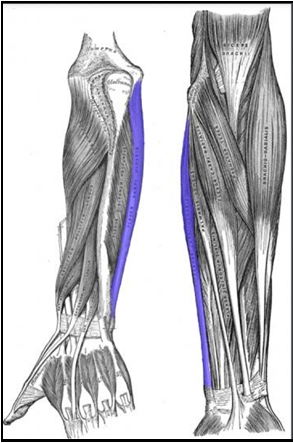

Bookshelver’s Tendinopathy in the Time of COVID-19 – Flexor Carpi Ulnaris Tendinopathy in a Librarian: A Case report